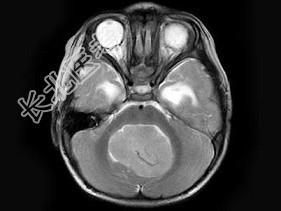

- 单项选择题男,2岁, 头痛、呕吐10余天,MRI检查如图所示, 最可能的诊断为 ( )

A、小脑蚓部髓母细胞瘤

B、星形细胞瘤

C、室管膜瘤

D、生殖细胞瘤

E、未见异常